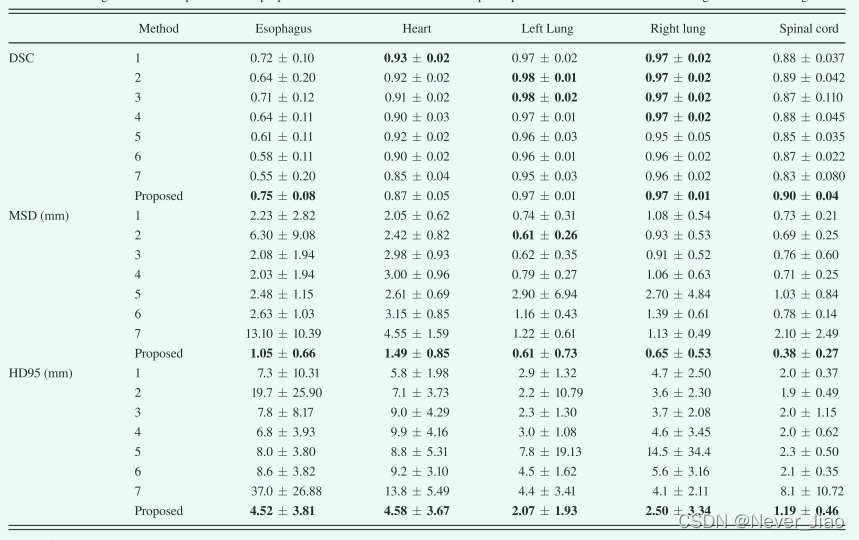

这项工作中使用的数据集是2017年AAPM胸部自动分割挑战获得的。参考文献 [35] 显示了来自七个研究所的细分结果。七个研究所中有五个开发了基于深度学习的方法,另外两个 (研究所 #4和 #6) 使用了基于多图谱的方法。我们将使用我们提出的方法的分割结果与七个组的结果进行了比较,并在表IV中列出了比较结果。我们的方法在双侧肺,心脏和脊髓上产生相似的DSC,但在食道分割方面优于所有七种方法。用所提出的方法获得的MSD和HD95在所有五个器官上均优于所有七种方法。

定量评估结果总结在图 5 和表 I 中。图 5 显示了对所有 35 名患者进行计算的六个评估指标——DSC、敏感性、特异性、HD95、MSD 和 RMSD,其平均值和标准差列于表中 I. 如图 5 和表 I 所示,所提出的方法在左肺、右肺和脊髓上实现了优异的分割精度,分别为 0.97、0.97 和 0.90 的平均 DSC,平均 HD95 为 2.07、2.50 和 1.19 毫米,所有平均 MSD 小于 1 毫米。由于图像对比度降低,心脏分割不如肺和脊髓分割简单。定量评估表明,所提出的方法与心脏描绘的基本事实非常吻合。平均DSC为0.87,平均HD95为4.58 mm,平均MSD为1.49 mm。在CT图像上,食管是五个器官中对比度最低的,因此最难描绘。提出的方法在食道分割上获得0.75±0.08 DSC、4.52±3.81 mm HD95和1.05±0.66 mm MSD。灵敏性评估真实的OAR体积与从该方法获得的体积重叠,而特异性量化真实体积之外的重叠部分。该方法的平均分割灵敏度为0.74–0.97,双侧肺最高,食道最低。这五种器官的特性几乎是一致的。五个器官的平均RMSD范围为0.8至3.1 mm。